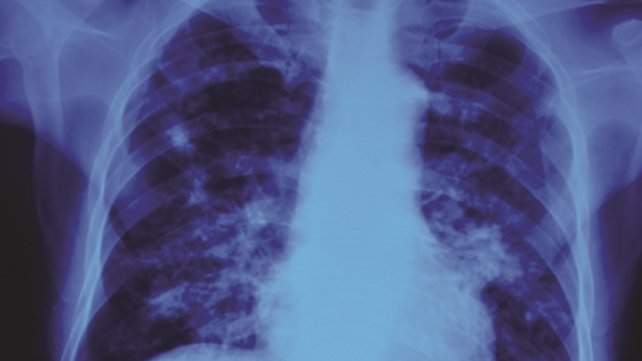

The RISE Clinic provides specialty consultation related to tuberculosis care in partnership with the Rhode Island Department of Health.

Staff members are experienced in tuberculosis care and know how to safely handle contagious patients. This includes treatment for those who have developed tuberculosis and for those persons who have been exposed and are at high risk of developing the disease in the future.